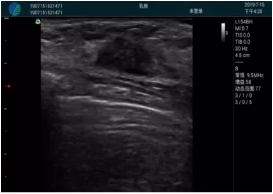

清晰顯示腺體內(nèi)低回聲快影,邊界清晰,包膜較光滑

確定進(jìn)針路徑并實時監(jiān)測抽吸針與腫塊位置關(guān)系

抽吸針進(jìn)入腫塊內(nèi)部進(jìn)行旋切

抽吸過程中可見腫塊明顯縮小,并根據(jù)腫塊位置改變針道位置

抽吸旋切后再進(jìn)行超聲復(fù)查,原腫塊區(qū)域未見殘留組織及出血